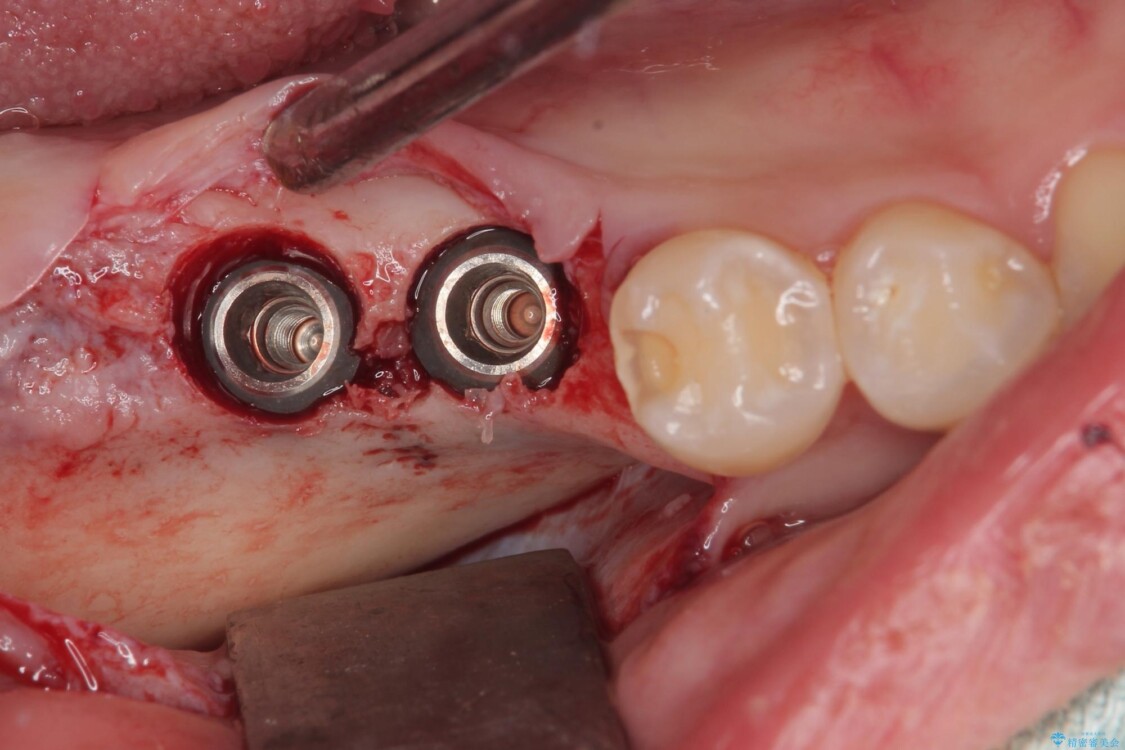

スペースが整った段階で、右下の第一大臼歯と第二大臼歯にインプラントを埋入。

治療途中

• 挺出歯を圧下してスペースを確保!目立たない部分矯正で下顎大臼歯にインプラント治療を実現 治療途中画像